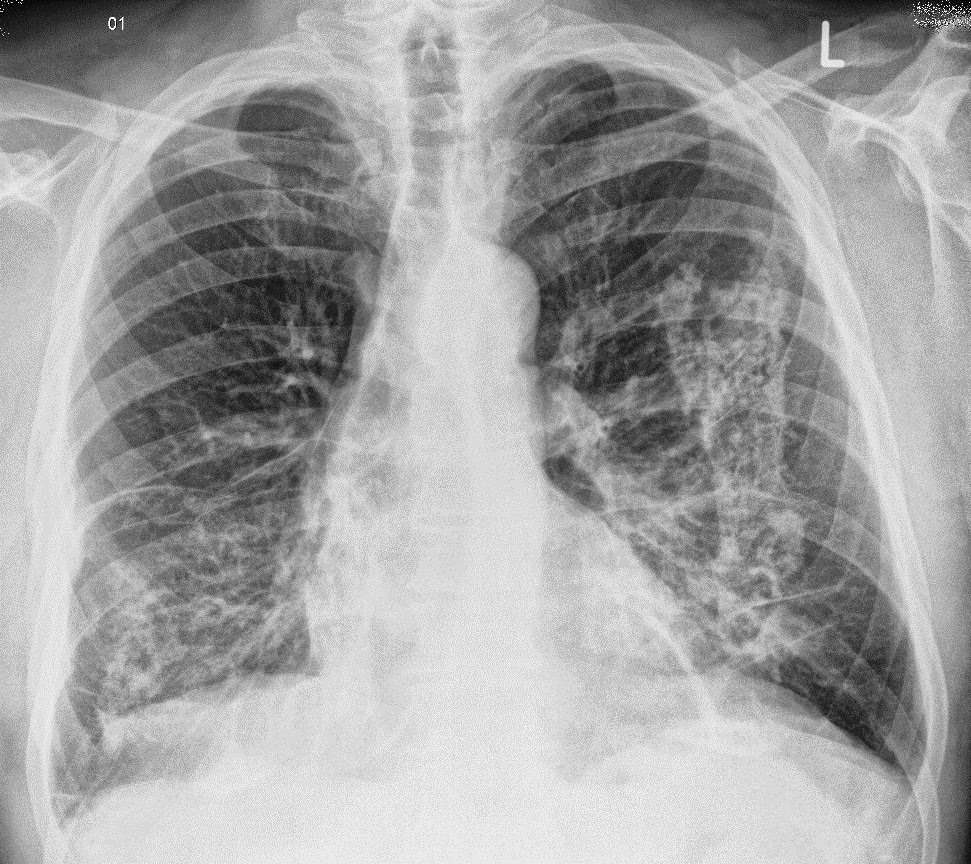

Rx tórax: inicial: infiltrado micronodular // tardio: fibrose em zonas superiores

Linfonodos com calcificação periférica, em casca de ovo (eggshell)

Mesotelioma (massa pleural): imagem hipotransparente em campo pulmonar superior direito, em contato direto com a parede torácica

Sinal da silhueta: hipotranparência apaga os bordos da estrutura adjacente, encostando na parede torácica